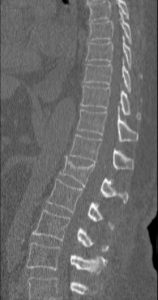

Las fracturas vertebrales en el contexto de un traumatismo de alta energía constituyen una patología quirúrgica compleja que debe tratarse en centros especializados.

Sin embargo, no resulta infrecuente valorar en consultas fracturas tratadas de manera conservadora cuyo dolor no ha remitido, asociadas o no a deformidad.

En otras ocasiones, un traumatismo o esfuerzo de baja energía (a veces puede pasar desapercibido) puede desencadenar una fractura, sobre todo si está asociada a osteoporosis, enfermedades reumáticas o enfermedades malignas.